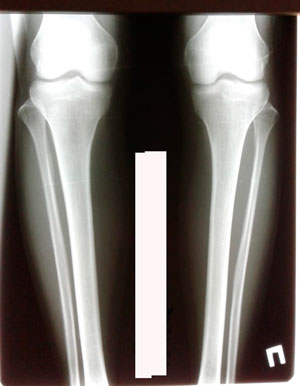

Исходник - 33 года.

Дата операции - 27.12.2019г.